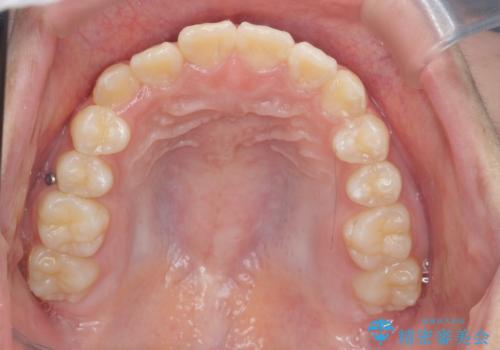

インビザラインで行う八重歯の治療

- 笑った時に目立つ八重歯の矯正治療を求めて来院されました。

マイクロインプラントを用いた臼歯の後方牽引、およびゴムかけ等の付加処置を駆使して八重歯の治療を行っていきます。

しっかりとゴムかけを頑張っていただいたおかげで、上顎臼歯の後方移動が達成されしっかりとした噛み合わせの構築と、八重歯の治療を達成することができました。